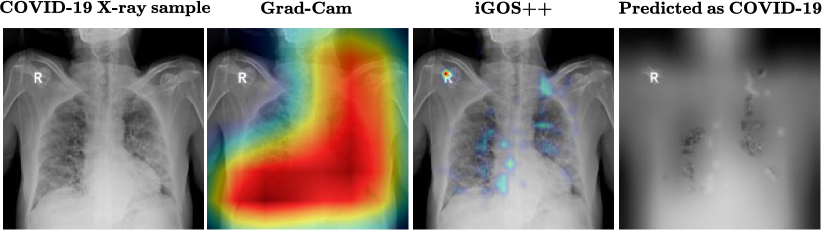

Somewhat surprisingly, when we applied iGOS++ on the trained classifier, we noticed that in occasional cases the classifier seems to have overfitted to singleton characters printed on the x-ray image (Fig. 5), such that even when only the character region is available, there is a non-negligible chance of classifying for COVID-19. Note that the higher resolution explanation from iGOS++ is important in pinpointing the heatmap to the character whereas low-resolution alternatives such as GradCAM were not informative. For further examples and the case when only text region is revealed to the classifier, please refer to the supplementary materials.

Refer to caption

Figure 5. Showcase of the capability of iGOS++ in detecting bugs in a COVID-19 classification pipeline. It can be noted that unlike Grad-Cam which provides coarse (8×\times8 resolution) and ineffective explanation, iGOS++ can generate a more-detailed explanation (32×\times32 resolution) to discover the most salient regions. In the right-most image, only by inserting the top 6% of the pixels from iGOS++ heatmap (highlighting the character “R”), the classifier predicts it as COVID-19 (confidence 43 %).